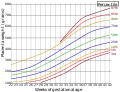

Close-up of umbilical attachment to fetal side of freshly delivered placenta Placenta weight by gestational age[58]

Placenta weight by gestational age[58] Ziheche (紫河车), dried human placenta used in traditional Chinese medicine